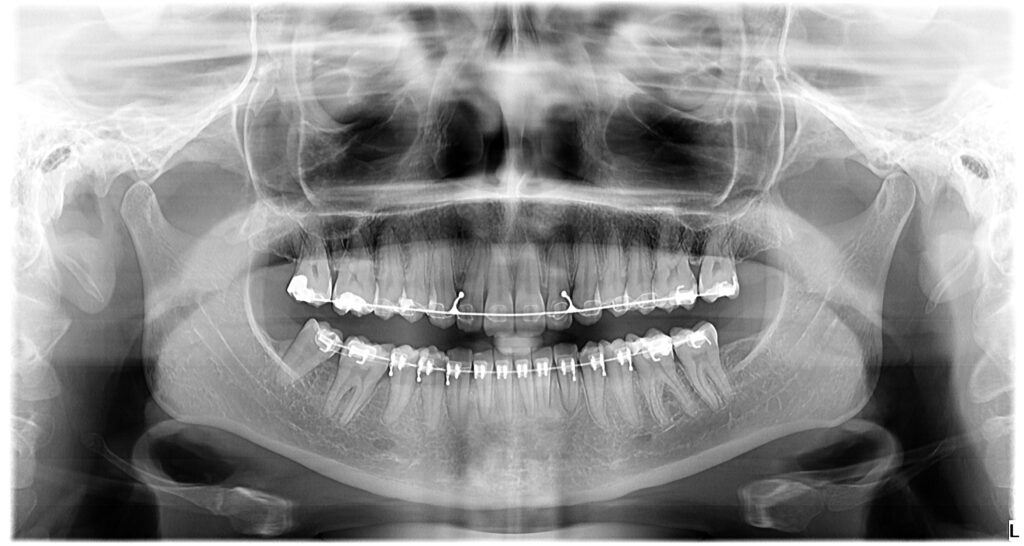

During an in-person visit, your orthodontist will closely examine dental records and take panoramic X-rays to identify potential problems below the surface. These are crucial steps of the treatment process that are usually left out when seeking mail-order orthodontic options.

In-person orthodontic treatments include the creation and examination of X-rays and comprehensive diagnostic records. Your teeth and mouth are unique, and examining your mouth with X-rays allows your orthodontist to see things below the surface, like jaw position, missing teeth, roots of your teeth, and the bone structure of your jaw. Knowing this information helps create a customized and detailed treatment, individualized for you. If an at-home orthodontic treatment provider answers “no” to this question, they are just creating a one-size-fits-most plan, that may not be the right one for you.